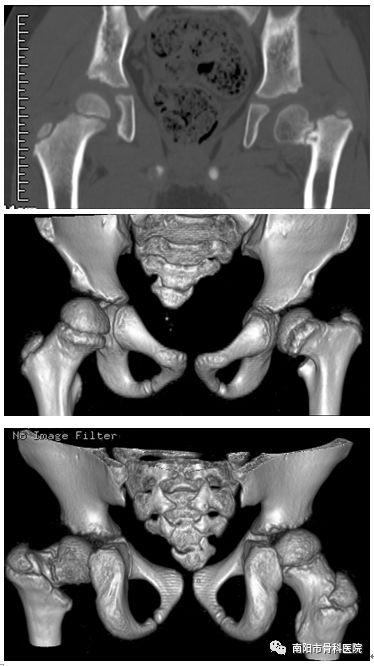

洪都中医院小儿骨科之大龄ddh患儿的保髋治疗病例分享

神助攻!1小时完成4岁女孩精准髋关节复位手术

髋内翻畸形股骨颈疲劳骨折行转子下截骨矫形

儿童常见畸形之髋关节发育不良

脑瘫儿髋关节脱位畸形的治疗求教

术前x光片可以明显看到左侧髋内翻畸形,股骨颈发育差 术后第3个月